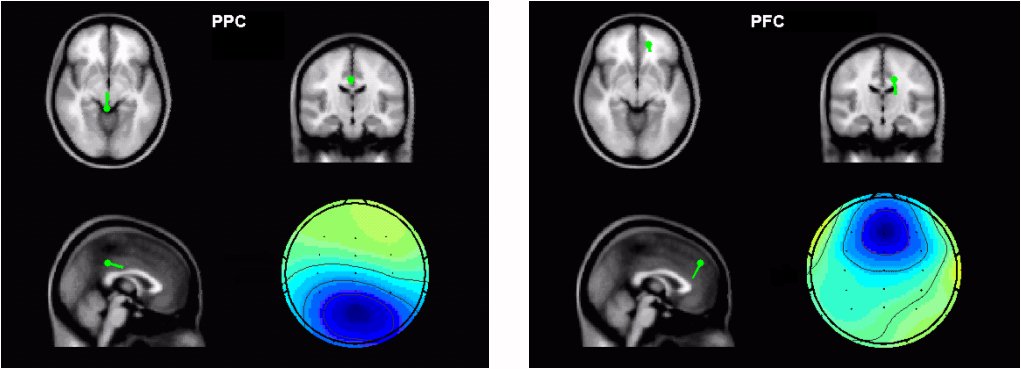

Figure 2. Typical scalp map and corresponding dipole location of a PPC component (left) and a PFC component (right) from the crossmodal matching task of one subject. Scalp maps are shown in color, while the averageMRI head model are shown in gray scale with green dipoles superposed on it, which were produced in EEGLAB [Delorme and Makeig, 2004].